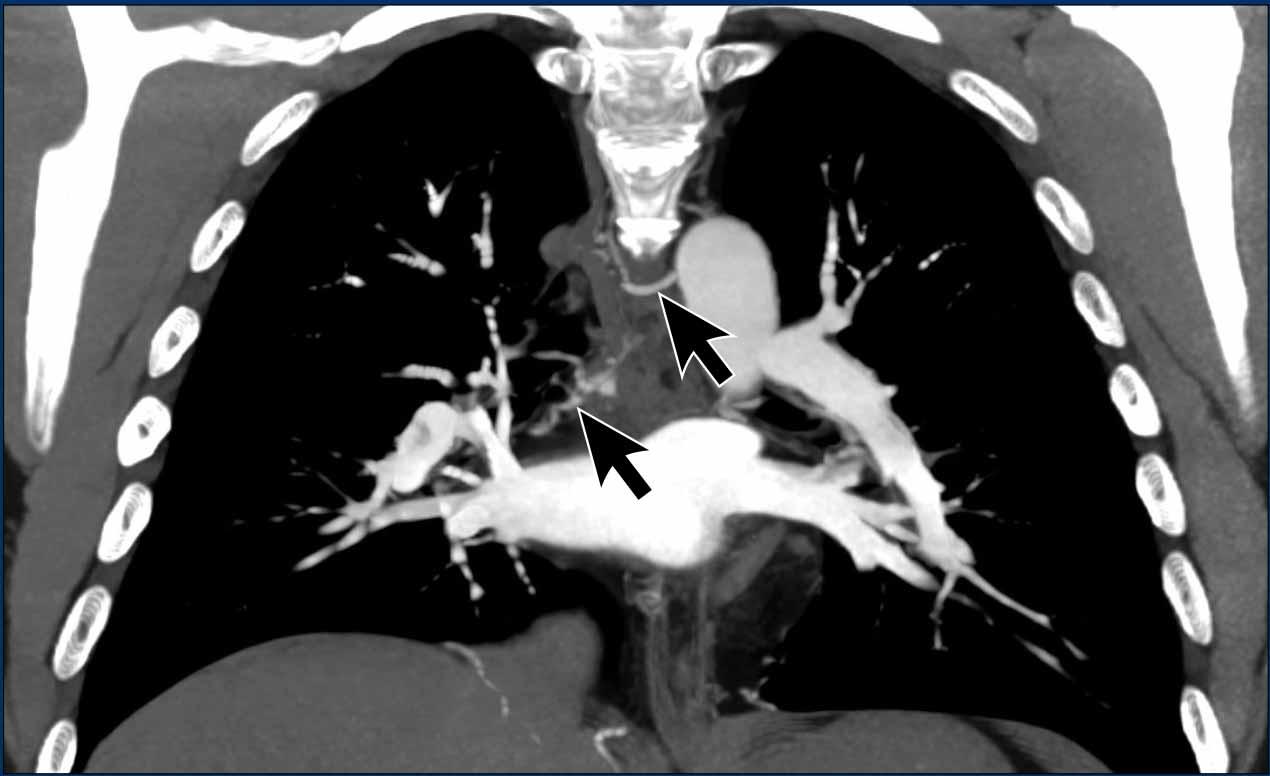

Tăng áp phổi do dị tật tim

Hồi lưu tĩnh mạch phổi bất thường một phần (PAPVR)

Trong hồi lưu tĩnh mạch phổi bất thường một phần, một hoặc nhiều tĩnh mạch phổi đổ về tuần hoàn tĩnh mạch hệ thống một cách bất thường (chủ yếu vào tĩnh mạch chủ trên ở bên phải, và vào tĩnh mạch tay đầu trái ở bên trái), thay vì đổ về nhĩ trái như bình thường.

Tùy thuộc vào thể tích luồng thông, tình trạng tăng tuần hoàn phổi mạn tính do luồng thông này có thể gây tổn thương nội mô, phì đại cơ trơn và xơ hóa mạch máu, cuối cùng dẫn đến tăng sức cản mạch phổi và hình thành tăng áp phổi.

Minh họa

Trong trường hợp này, hầu hết các tĩnh mạch phổi đổ về nhĩ trái theo đường bình thường (mũi tên xanh).

Tuy nhiên, tĩnh mạch phổi thùy trên phổi phải đi theo đường bất thường và đổ qua tĩnh mạch chủ trên vào nhĩ phải thay vì nhĩ trái (mũi tên đỏ).

Hồi lưu tĩnh mạch bất thường này tạo ra luồng thông trái-phải, dẫn đến tình trạng quá tải thể tích của nhĩ phải và thất phải.

Các hình ảnh này thuộc về một bệnh nhân tăng áp phổi thứ phát do hồi lưu tĩnh mạch phổi bất thường một phần (PAPVR).

Đặc điểm hình ảnh

Các tĩnh mạch phổi thùy dưới phổi phải không kết nối với nhĩ trái (LA) mà thay vào đó đổ vào tĩnh mạch chủ trên (mũi tên).

Lưu ý tình trạng giãn hai bên của các động mạch phổi, phù hợp với tăng áp lực động mạch phổi.